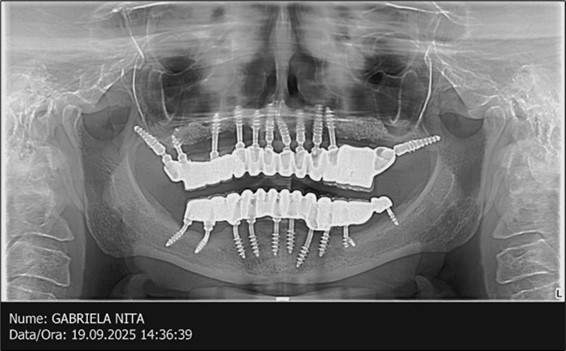

A total of 11 implants is placed in the maxilla, including compressive TPG implants with a polished surface in the maxillary-sphenoid fusion area (Figure 3, Figure 9). Similarly, in the anterior region, final fixation is achieved in the nasal cortex, and BCS corticobasal implants are added in areas with massive bone loss in the frontal region (Figure 3, Figure 8, Figure 11). Additionally, in the palatal sinus cortical area, with the aim of avoiding the addition and sinus lift zone where the second cortical bone no longer exists, 3 implants are placed, 2 in quadrant 1 and 1 in quadrant 2 (Figure 3, Figure 8). Through the Caldwell-Luc sinus lift procedure, the sinus cortical bone is displaced to allow the placement of the graft material and elevation of the sinus membrane. This sinus cortical is no longer recreated at the junction of the graft material and mucosa-sinus membrane, making it impossible to place a corticobasal implant, which relies on the second cortical bone. In the distal mandibular area, after the removal of two stage implants due to massive destruction in quadrant 3, implant placement distal to the mylohyoid line is not possible, as in quadrant 4 (Figure 10). A re-intervention occurs after 5 months to stabilize the area (Figure 12, Figure 14). Also, at the moment of fixation, the tip of one implant fractures, and the decision is made to leave it in place due to regional bone destruction, in order to avoid enlarging the bone defect.

In the interforaminal area (Figure 3, Figure 13), 6 corticobasal implants are also placed. The increased number of implants is due to the poorly represented distal area that needs to be compensated.

Figure 3.Panoramic pictures after removal of implants affected by peri-implantitis, extractions, alveolar crest regularization, and insertion of corticobasal and TPG implants (07.2022)

The results of rehabilitation treatment with corticobasal and compressive implants with a polished surface after the failure of two stage implants were highlighted over a period of 3 years and 3 months as being very good (Figure 14, Figure 15), with the patient completing a satisfaction survey in this regard. Certainly, it is necessary to continuemonitoring these results in the long term.